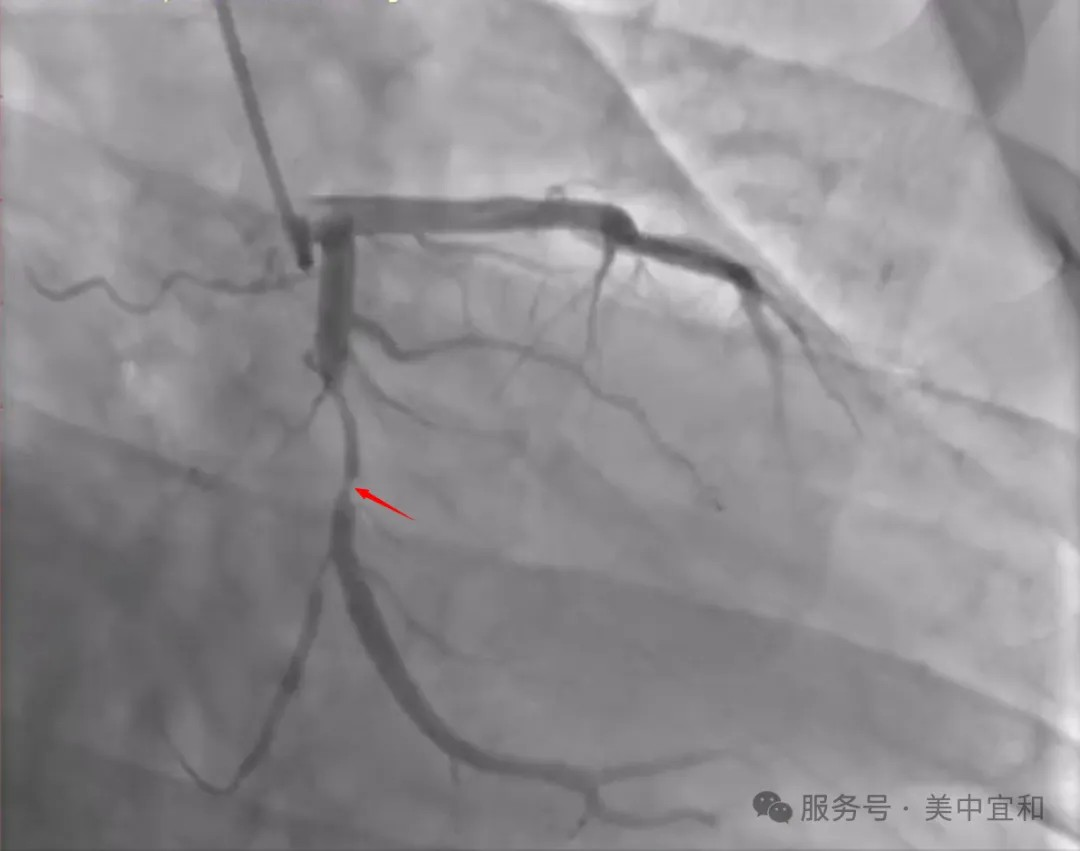

又(yòu)來一(yi)箇(ge)30多(duo)歲的(de)冠心病??看到(dao)汪先(xian)生(sheng)的(de)病歷(li)時,宜咊(he)醫(yī)院心內(nei)科(ke)顔主(zhu)任不由得皺起了(le)眉頭,這昰(shi)汪先(xian)生(sheng)“二進(jin)宮”了(le),兩箇(ge)月前(qian),他(tā)突髮(fa)胸痛、胸悶,伴随着背痛、憋氣(qi),在(zai)傢(jia)人(ren)勸說下